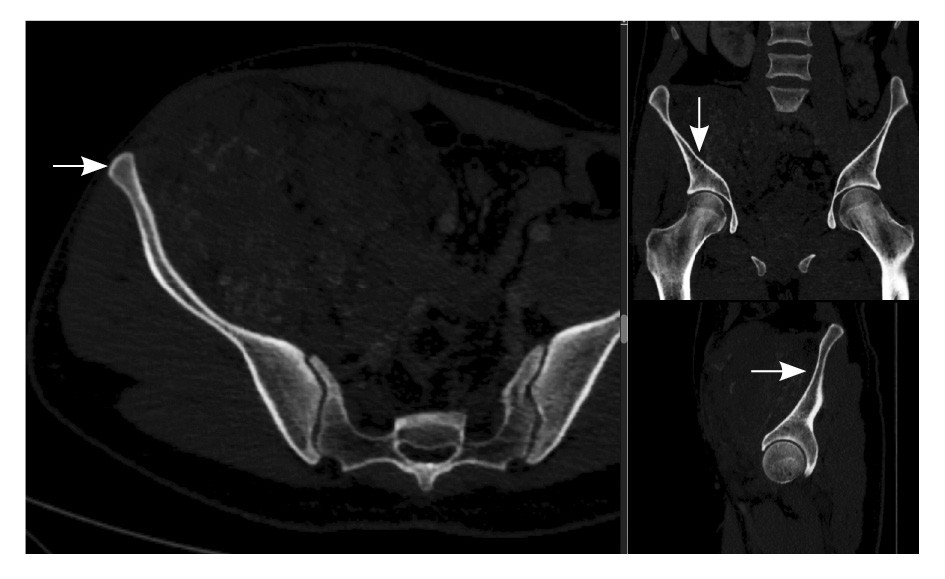

Рис. 2. Мультиспиральная компьютерная томография органов брюшной полости и забрюшинного пространства, режим костного окна. Кортикальный слой правой подвздошной кости прослеживается равномерно на всем протяжении, без признаков деструкции (стрелки)

Отсутствие инфильтративно-деструктивного характера роста образования, а также наличие в его структуре сосудистых лакун позволило предположить сосудистый генез опухоли и в большей степени – венозно-кавернозную форму ангиодисплазии, нежели злокачественное образование.

Близкое расположение внутримышечных гемангиом к костям приводит к контактным изменениям последних. Методами лучевой диагностики выделяют три типа изменений костных структур – периостальные, кортикальные и медуллярные. Близость расположения образования к кости статически значимо коррелирует с любым типом костной реакции, а размер образования – лишь с медуллярным [14]. Агрессивный тип периостальной реакции и деструкция кортикального слоя могут быть ошибочно приняты за первичную опухоль кости [6, 15]. Однако эти изменения факультативны: так, в нашем исследовании никаких изменений костных структур отмечено не было.